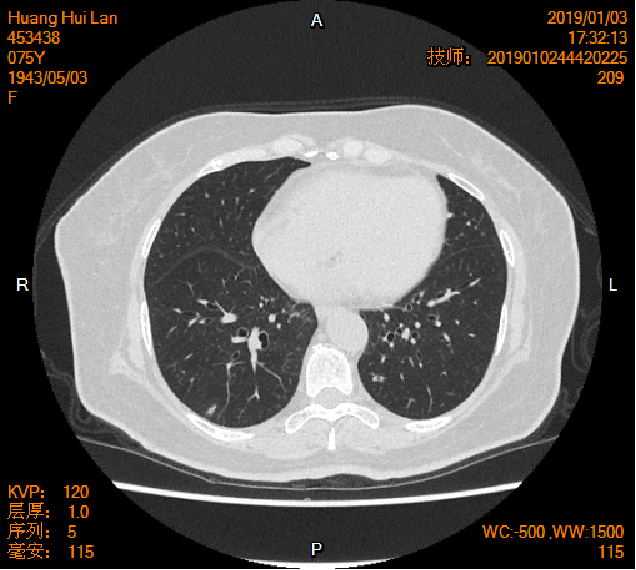

2019-01-04胸腹盆CT